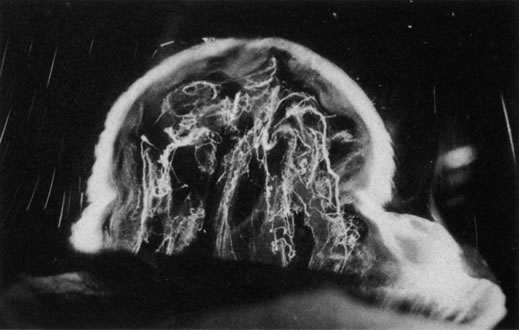

There are no clearly identified vitreous changes during stages I and II of acute ROP, although this may simply be due to our present inability to detect such abnormalities.51 Indeed, the abundance of reactive oxygen species in the retina and vitreous of premature infants could induce widespread vitreous liquefaction.52 There are also likely to be localized areas of liquid vitreous, particularly at the periphery. At surgery for stage IV-A ROP with retinal detachment, there is a “trough” in the periphery.53 This structure is most likely the consequence of underlying retinal immaturity in the periphery, with consequent lack of typical gel vitreous synthesis, normally a Müller cell function, overlying the immature retina. The liquid vitreous trough is probably present early in the natural history of disease but goes undetected by present vitreous imaging techniques.54 Such disruption of normal vitreous composition and structure probably alters a number of physiologic processes within the vitreous, including the ability of vitreous to inhibit cellular and vascular invasion.9–11 Furthermore, the interface between posterior gel vitreous and peripheral liquid vitreous at the ridge causes vitreous traction to be exerted at the retinal ridge.

In stage III ROP, new blood vessels extend from the inner retina into the vitreous cortex. The cortex, overlying the rear guard of differentiated capillary endothelial cells, becomes opaque and contains linear, fibrous structures adjacent to a large pocket of liquid vitreous.55 In advancing from stage III to stage IV, the neovascular tissue arising from the rear guard grows through the vitreous body toward Wiegert's ligament on the posterior lens capsule.56 This configuration of neovascularization is probably the result of cell migration and proliferation along the walls of the future Cloquet's canal or the tractus hyaloideus of Eisner. Cells of the primary vitreous likely contribute to the formation of the dense central vitreous stalk and retrolental membrane seen in the cicatricial stage, since these cells could also undergo migratory and proliferative responses to intraocular angiogenic stimuli.